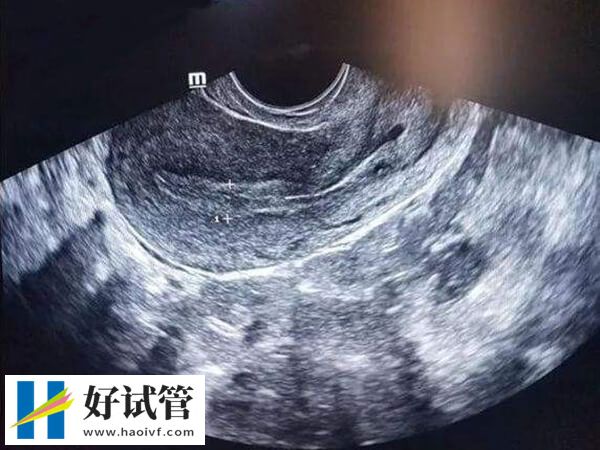

试管婴儿移植前,合适的内膜形态对于移植的成功率和胚胎的着床有着重要影响。一般来说,A型内膜形态最好,其移植胚胎后更容易着床,这是因为该内膜厚度在7mm以上,有明显的三线征,此时受孕几率较大,不过因个体差异较大,部分患者内膜为bc时,也可以进行胚胎移植。

由于胚胎是在子宫内膜上着床的,所以在试管移植前,医生会反复检查女性的子宫内膜状态,只有符合标准了才会同意移植。而临床上将内膜分为了a、b、c三个等级,那么内膜abc哪个更容易着床,对此感兴趣的患者可以参考下列内容:

a型内膜出现在卵泡中期,此时,随着雌激素的不断刺激,子宫内膜逐渐增厚,大约在八毫米,构成三线征a型。如果这时子宫内膜厚度在8-12mm左右,那么此时移植后的受孕几率较大,移植成功率有明显提高。

B型内膜厚度在9-12mm之间,这种类型的内膜含有丰富的血管,雌激素水平较高,标志着接近排卵期,因此更适合胚胎着床。一般B型子宫内膜对于冷冻胚胎移植的妊娠率是比较高的。

C型内膜厚度在10-14mm之间,通常出现在排卵后黄体期,这个时期的内膜虽然厚度适中,但由于其分泌期的特性,可能不利于胚胎的着床。不过对于这种情况,可以通过药物治疗或其他医疗手段来调整,以达到更适合移植的状态。